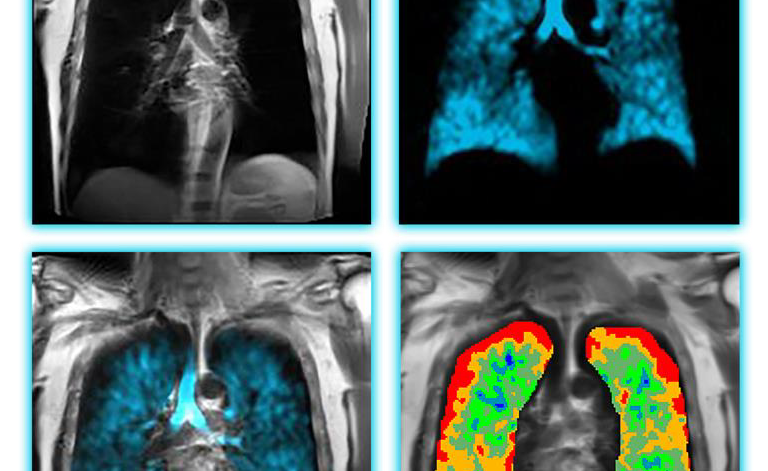

Polarean Imaging 公司與上鉅實業股份有限公司2025/3/2正式簽署代理協議,將Polarean創新性的氙氣Xenon MRI平台引進台灣。